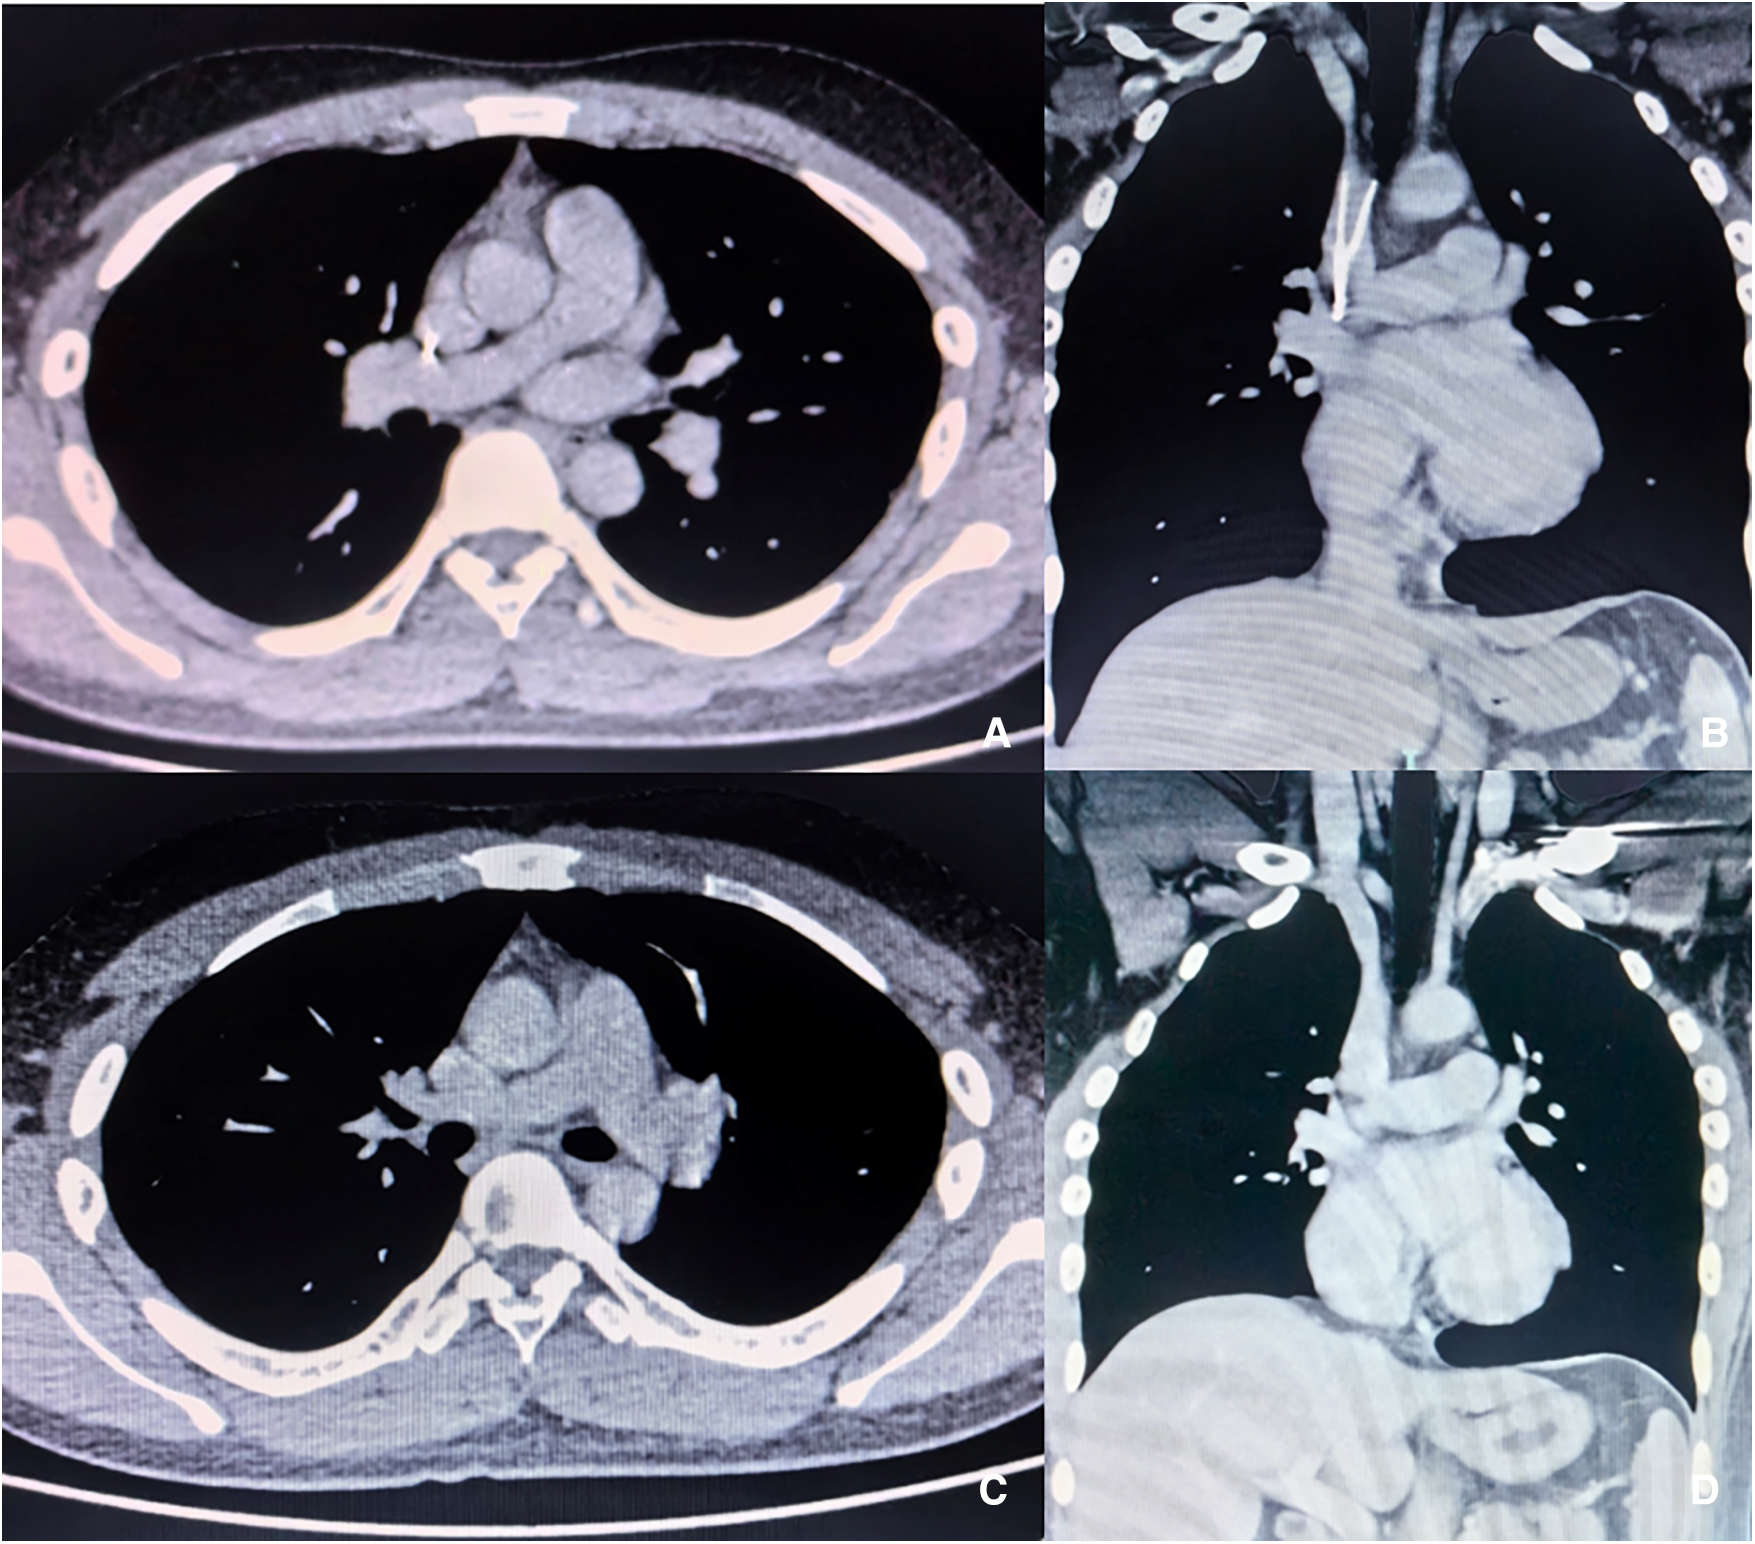

No PE was detected via computed tomographic pulmonary angiography (CTPA), the SVC was patent, and no haematoma formation. The filter retraction hook was likely to penetrate the SVC wall, and its tip was very close to the right pulmonary artery (Figures 1A,B). Colour Doppler ultrasound revealed no thrombus in the deep veins of either upper limb. No pericardial effusion was observed in echocardiography, nor arrhythmia in electrocardiogram. The surgical indications for filter removal were met, and the patient had strong desire for filter removal surgery. The procedure plan was designed as follows: the modified loop-snare technique (12) was firstly attempted to remove the filter; open surgery was a back-up when endoluminal therapy failed or complications occurred.

Figure 1

Enhanced CT images before and after procedure. (A,B) The filter retraction hook entered SVC wall, and the tip was close to the right pulmonary artery. (C,D) No haematoma, dissection or cardiac fluid accumulation in the superior vena cava or right pulmonary artery after filter removal.

CTPA (Figures 1C,D) was performed one week after the procedure. No pericardial effusion or pleural effusion was observed, no haematoma was found in the SVC, and no right pulmonary artery dissecting aneurysm or intramural haematoma was observed. PE did not occur in perioperative period, and anticoagulant therapy with 20 mg of rivaroxaban QD was recommended after the procedure (14). There was no recurrence of upper extremity DVT, no SVC thrombosis, and no symptoms related to PE during the 3-month follow-up.